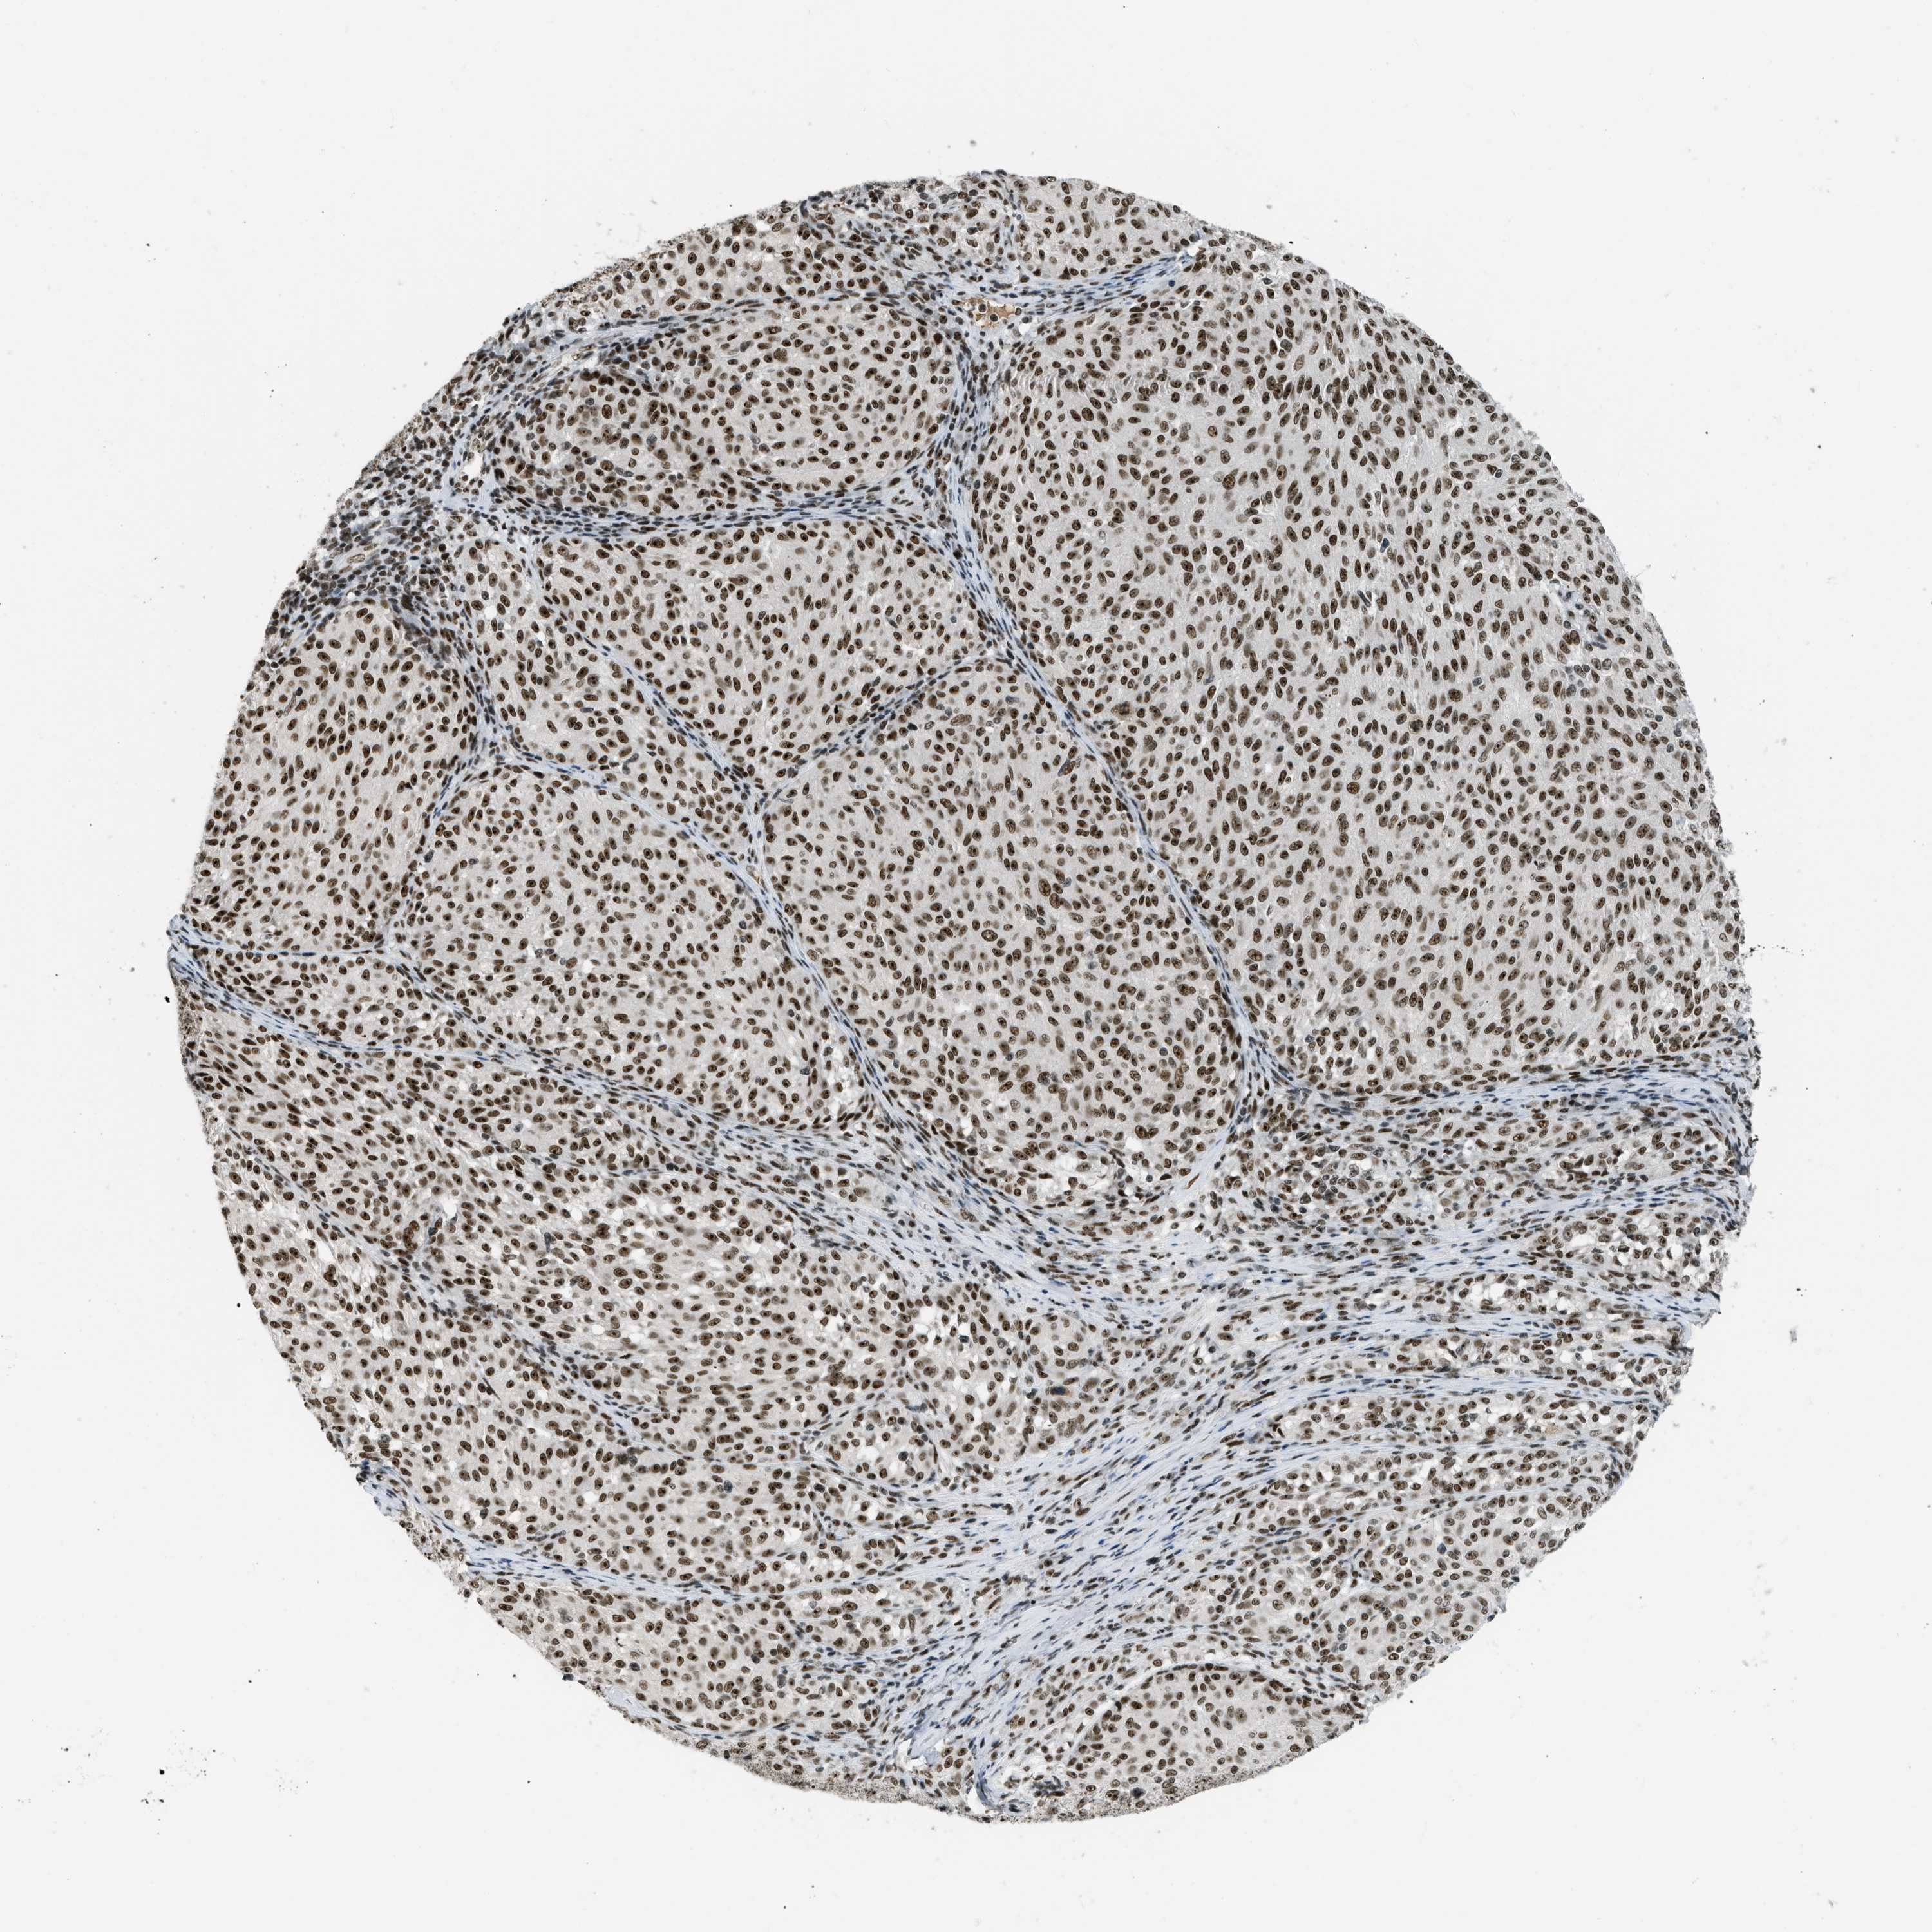

MELANOMA - Protein expressioni

A mouse-over function shows sample information and annotation data. Click on an image to view it in a full screen mode. Samples can be filtered based on level of antibody staining by selecting one or several of the following categories: high, medium, low and not detected. The assay and annotation is described here.

Note that samples used for immunohistochemistry by the Human Protein Atlas do not correspond to samples in the TCGA dataset.

Antibody stainingi

Antibody staining in the annotated cell types in the current human tissue is reported as not detected, low, medium, or high, based on conventional immunohistochemistry profiling in selected tissues. This score is based on the combination of the staining intensity and fraction of stained cells.

Each image is clickable and will lead to virtual microscopy that enables deeper exploration of all samples and also displays staining intensity scores, fraction scores and subcellular localization as well as patient and tissue information for each sample.

Antibody HPA018334

Staining

High

Medium

Low

Not detected

Intensity

Strong

Moderate

Weak

Negative

Quantity

>75%

75%-25%

<25%

None

Location

Nuclear

Cytoplasmic/membranous

Cytoplasmic/membranous,nuclear

Malignant melanoma, Metastatic site